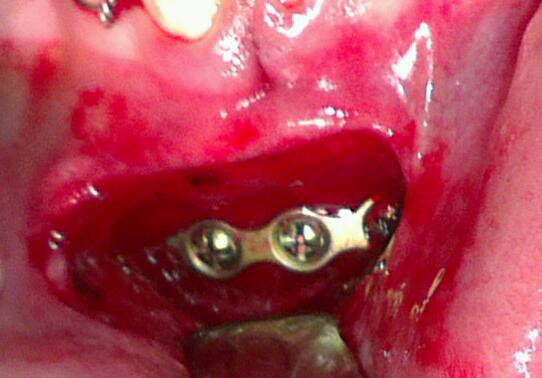

Results: The most frequent bone fractured was the mandible, which accounted for 106 cases 49.5%, followed by 15.4% of pan facial (full house) fractures and 15.4% of Zygomatic complex fracture. The associated mid face fractures were found in 12.6 % and isolated nasal bone fractures were found in 1.5% cases. The most common cause of injury was RTAs 58.4%, followed by accidental falls 24%, FAIs 6.1%, interpersonal violences 2.8% and sports and other injuries were 8.4% cases. Employees 49.5% and students 31.3% in age groups 20-40 years are mostly affected by RTA, while falls 14.4% are more common in age group less than 20 years. ORIF alone 43.9%, MMF±suspension 38.8% and ORIF with MMF 14.5% cases were the main mode of treatment in our centre.

Conclusions: In this case series, mandible was the most commonly fractured facial bone; RTAs especially by motorbike and chigchi rikshaw were the most common etiological factors. Results could be influenced by the personal and working environment.

IMAGES